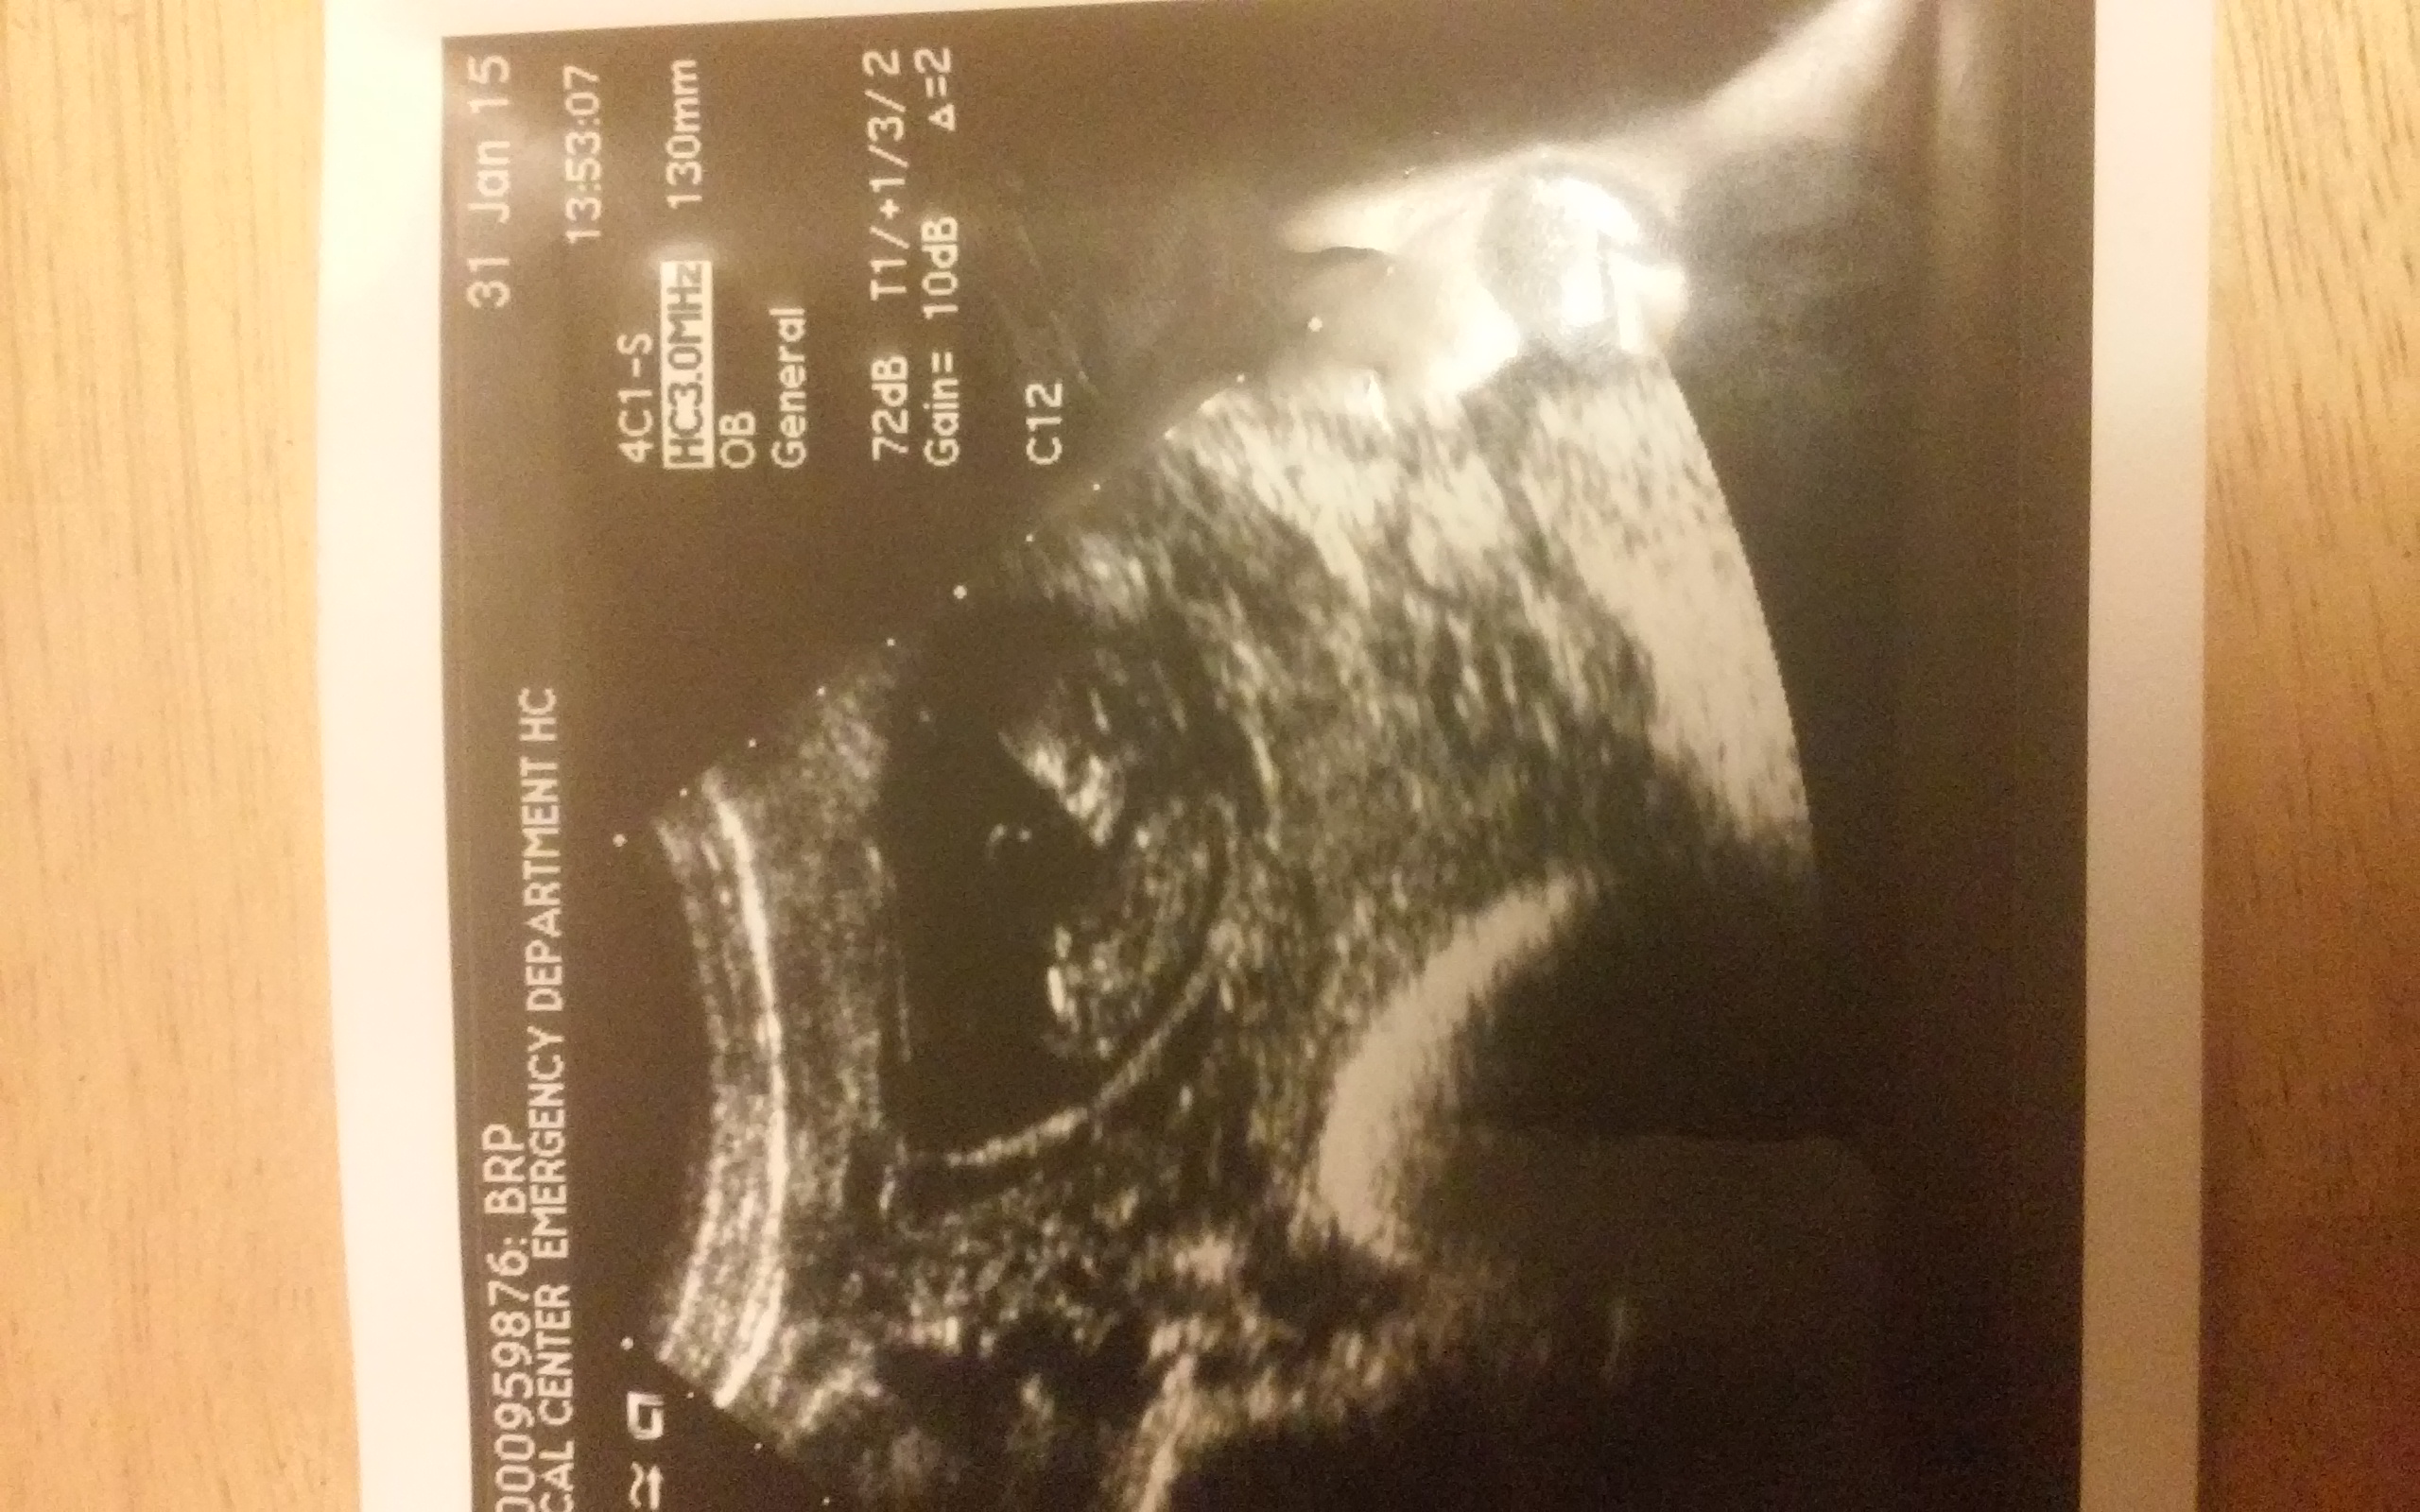

Okay another site blew this up & two ladies said boy..Its actually 11wks and 4 days...Iam really hoping for a girl but want honest answers..3d 4d ultrasound next Thursday..Any thoughts? I will post confirmation.

11+4 is way to early to guess - they pretty much look the same x